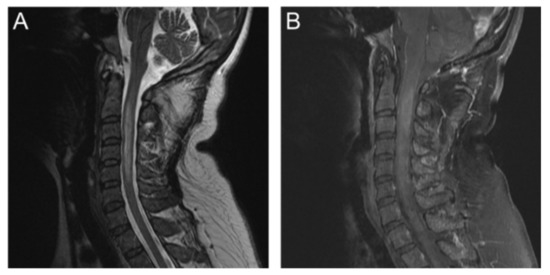

Magnetic-Resonance Diffusion-Tensor Tractography in the Diagnosis of Tumefactive Spinal-Cord Lesions in Neuromyelitis Optica

2. Case Report